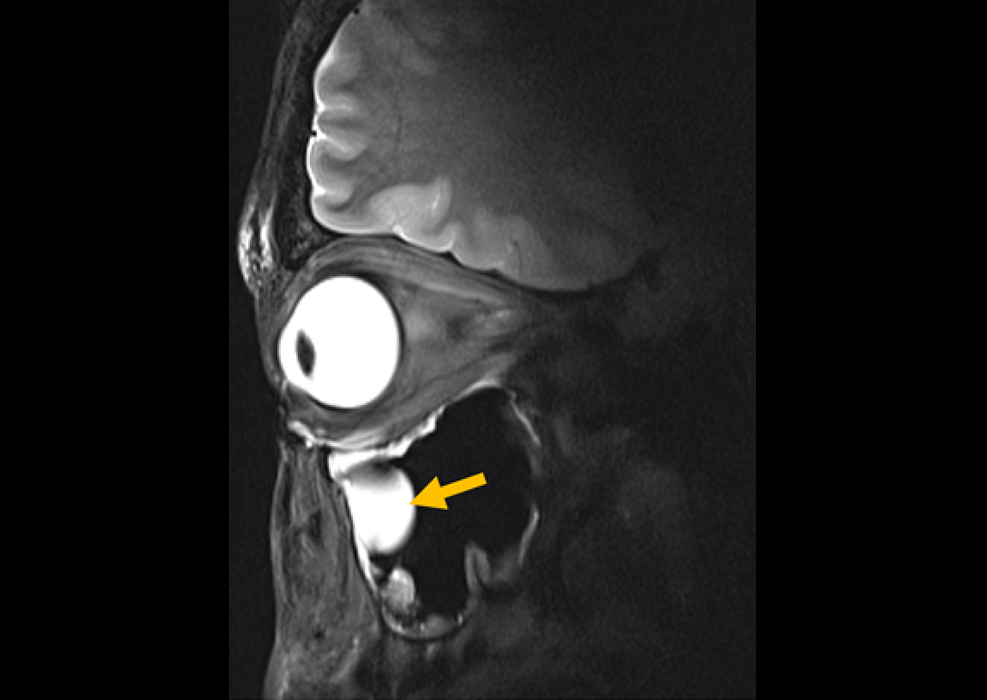

Nuevo enfoque de imagen para mejorar el tratamiento de lesiones de la médula espinal